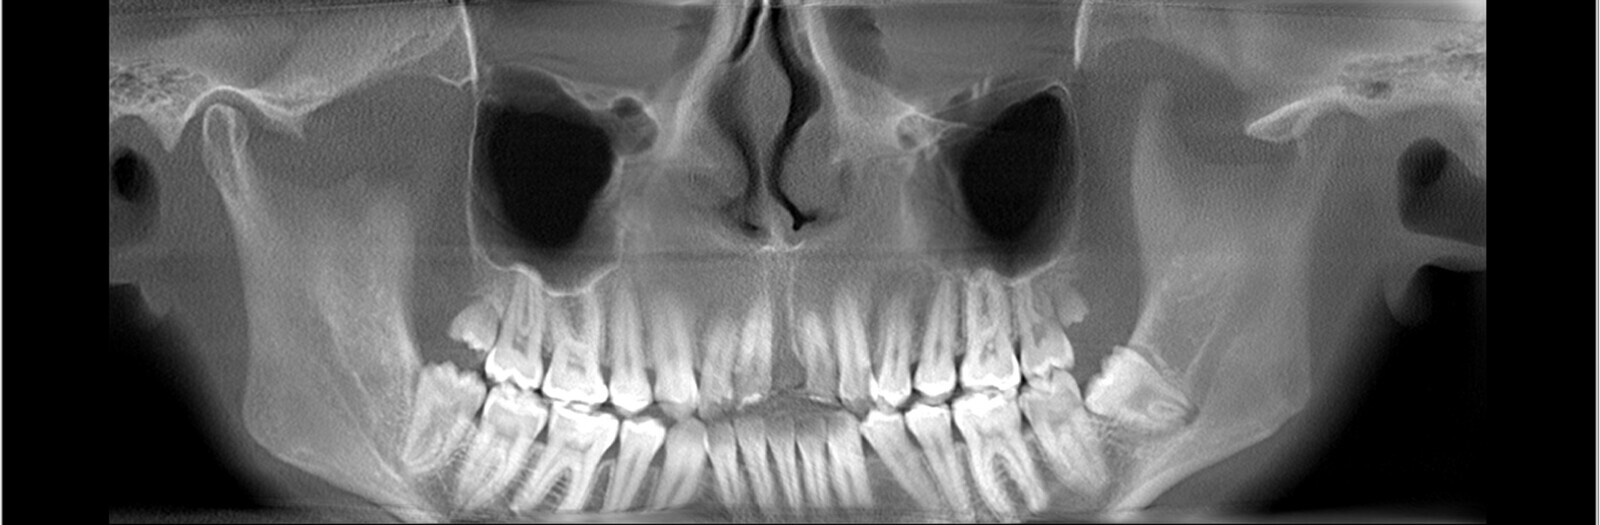

Ryc. 2_TK przedzabiegowe.